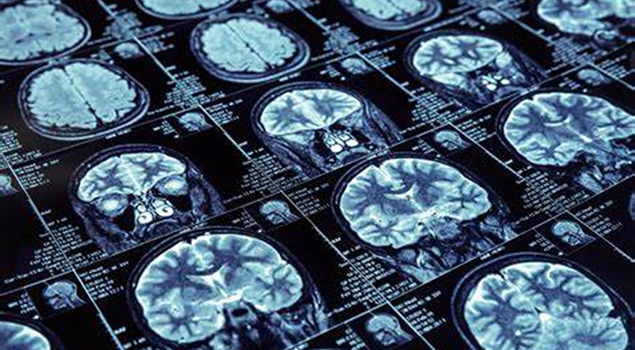

Therefore, the construction of regional image center makes patients enjoy the remote image diagnosis of superior hospitals without leaving the home. It not only reduces the misdiagnosis / missed diagnosis rate of the basic hospitals, but also helps to improve the diagnosis

The level of diagnosis and treatment of imaging physicians. It is conducive to the formation of sustainable development trend of complementary and shared resources such as talents, technology, equipment, medical treatment, scientific research and teaching